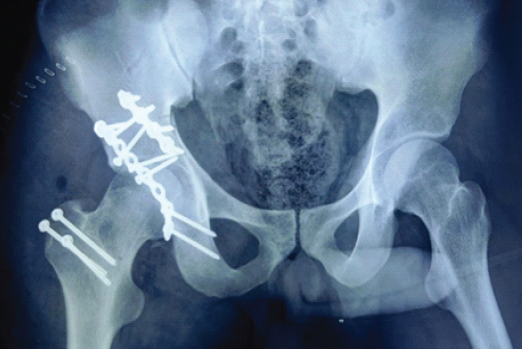

Total Hip Replacement Following Unsuccessful Acetabular Repair: A Case Report

Alok Chandra Agrawal , Harshal Sakale , Nirmal Rathi , Rakesh Dhaka , Somok Banerjee , Devashish Singh

………………………………p.22-26